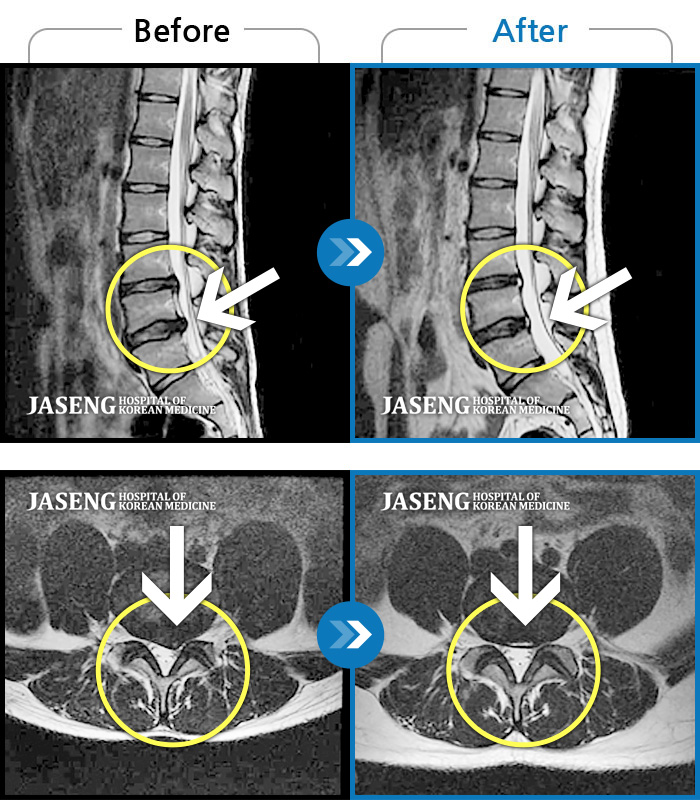

MRI사진에서 좋아지고 있다는 말씀에 넘 기뻤습니다^_^

제가 가지고 간 MRI 영상자료를 보시면서 수술하지 않고도 충분히 고칠수 있다는 희망적인 말과 증상에 대해 자세히 설명해주시고 앞으로 어떻게 치료할 것인지에 대하여 알기쉽게 설명해주셔서 감사했습니다.